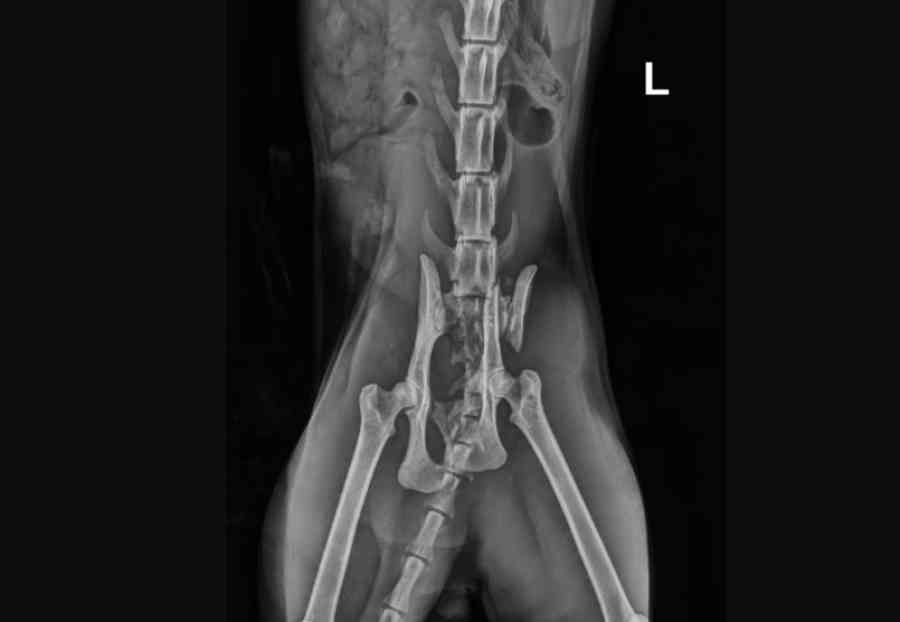

Seine Hüfte ist komplett zertrümmert, die Schmerzen müssen unvorstellbar gewesen sein. Doch Fridolin hat gekämpft. Und er kämpft noch immer.

Aktuell befindet er sich stationär in tierärztlicher Behandlung. Die Diagnose ist ernst – und der Weg zurück ins Leben wird lang. Fridolin braucht jetzt 8 bis 10 Wochen strikte Boxenruhe, regelmäßige Kontrolluntersuchungen, Schmerztherapie, intensive medizinische Versorgung und tägliche Pflege. Dazu kommen mögliche Folgebehandlungen, Medikamente und ein enormer Betreuungsaufwand.